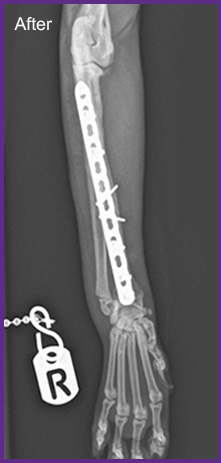

我們提供留院服務並擁有相應的治療設施,亦是小數備有CT電腦掃描及MRI磁力共振等大型醫療儀器的診所及醫院。